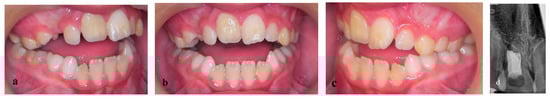

2. Materials and Methods